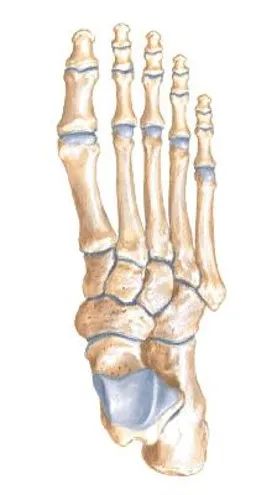

整个关节结构可以划分为三个柱:

• 内侧柱:第一跖骨和内侧楔骨

• 中柱:第2、3跖骨和中外侧楔骨

• 外侧柱:第4、5跖骨和骰骨

第二跖骨基底部深入到3个楔骨形成的马蹄形凹槽中,在跖跗关节的稳定性中起重要作用。

跖骨的基底及楔骨、骰骨形成一拱形结构,也有较好的稳定作用。